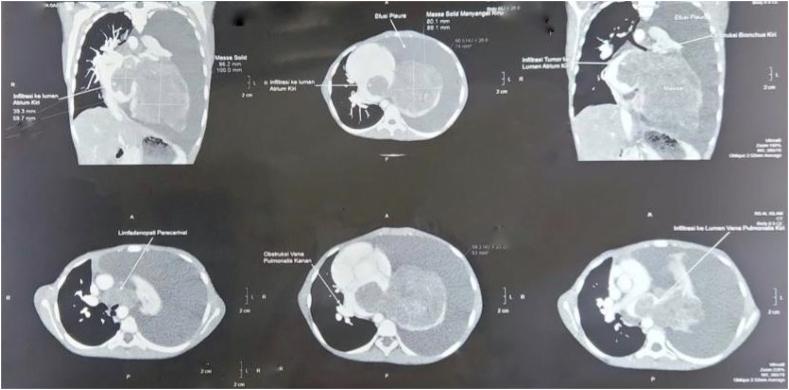

An 11-year-old girl presented at an emergency department with two months of progressive dyspnea with malnutrition. A fused mass was found in LA on an echocardiogram along with moderate MR, severe MS, and mild pericardial effusion. CT scan showed a massive pleural effusion with a solid mass in the left lung obstructing the left bronchial tree, accompanied by the expansion of the tumor mass into the left pulmonary vein and LA.

一名11岁女童因进行性呼吸困难2个月伴营养不良就诊于急诊科。超声心动图显示左心房有一个融合性肿块,伴有中度二尖瓣反流、重度二尖瓣狭窄和轻度心包积液。CT扫描显示大量胸腔积液,左肺有一个实性肿块阻塞左支气管树,同时肿瘤肿块延伸至左肺静脉和左心房。